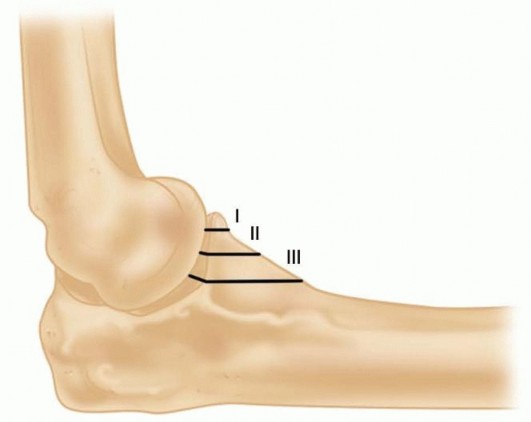

Coronoid fractures are equally critical to evaluate, as the coronoid provides the anterior buttress preventing posterior subluxation of the ulna. These have been traditionally classified by Regan and Morrey: Type I (tip avulsions, often representing capsular avulsions rather than true osseous stabilizers), Type II (less than 50% of the coronoid height), and Type III (more than 50% of the coronoid, often involving the sublime tubercle and MCL insertion). However, modern biomechanical understanding emphasizes the anteromedial facet fracture, a distinct entity caused by a primary varus force. The medial facet is paramount for varus stability of the elbow. These fractures are inherently unstable and are best treated with open reduction and internal fixation utilizing a medial buttress plate, as failure to recognize and stabilize the anteromedial facet will lead to rapid articular wear and chronic varus instability.

Step 1: Fix the Coronoid Fracture. The coronoid is addressed first, often through the lateral traumatic window after the fractured radial head fragments have been temporarily excised or retracted. Small transverse tip fractures (Type I) are often capsular avulsions and can be secured using heavy nonabsorbable sutures passed through the anterior capsule and tied over the dorsal aspect of the proximal ulna via drill holes (the "capsular lasso" technique). Larger fragments (Type II) can be fixed with retrograde cannulated screws from the dorsal ulna. Anteromedial facet fractures demand a medial approach and rigid fixation with a mini-fragment buttress plate to resist varus shear forces.